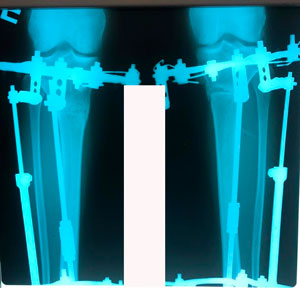

Пациентка - 37 лет.

Дата операции - 24.10.2019г.

Диагноз: варусная деформация голеней. Ротация с обеих сторон.